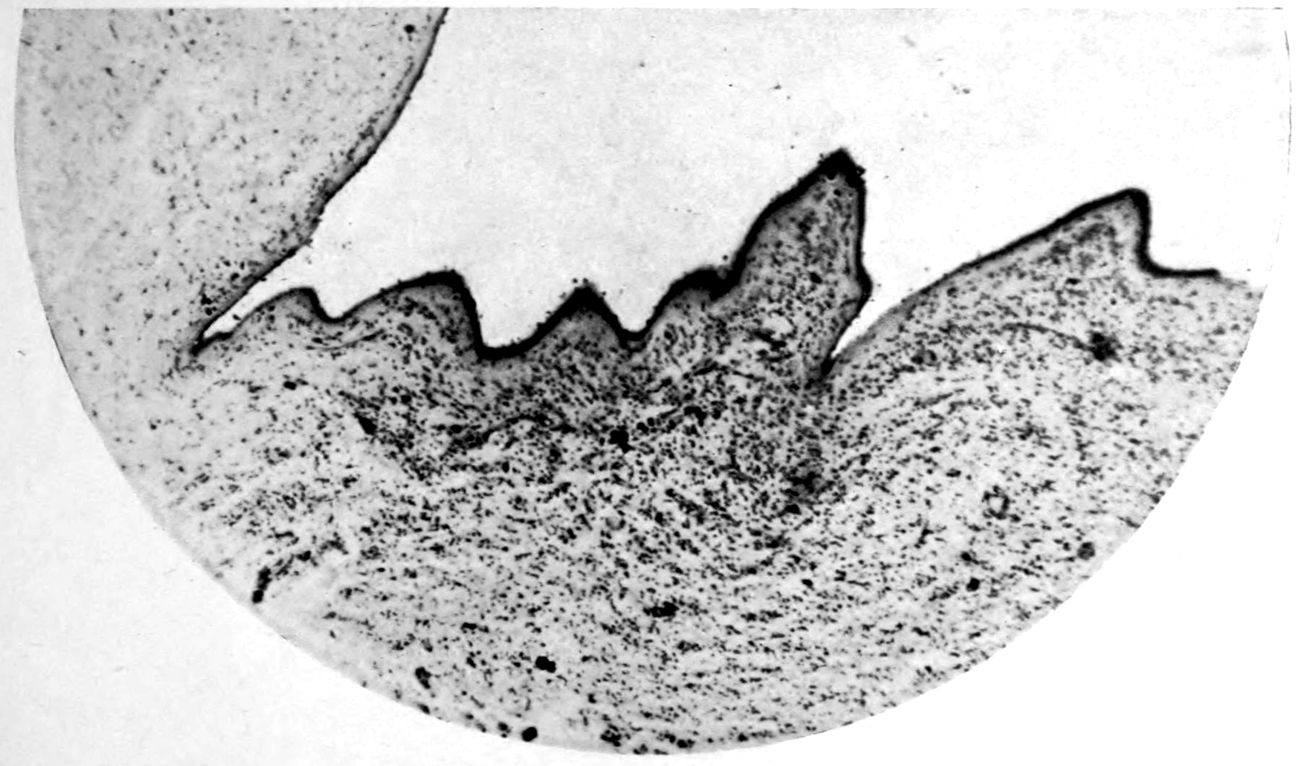

A. Normal postcentral cortex. (Compare B.)

B. Nerve cell losses. Perivascular deposits of mononuclear cells, amongst which are numerous plasma cells. Note decrease in number of nerve cells. Note irregular disposition of nerve cells. From paretic neurosyphilis.

Microscopic findings are here presented merely in sufficient detail to establish the diagnosis. The left superior frontal gyrus shows extensive and somewhat irregular cellular and fibrillar gliosis of the plexiform layer, together with an increase of thickened vessels having lymphocytes and plasma cells in their sheaths.

The perivascular infiltrations are most extensive in the lower layers of the cortex. The lamination is in places thoroughly obscured, except that representatives of the layer of large external pyramids are almost always demonstrable.

The layer of medium-sized pyramids has undergone more numerical loss of elements than have the other layers.

Gliosis of white matter.

Specimens from the cerebellum show a destructive process of great severity, but a little irregular in extent, affecting chiefly the Purkinje cell belt. The Purkinje cells are often absent throughout one side of a given lamina, and there has ensued a dense accumulation of neuroglia cells along a former Purkinje cell belt, together with a considerable gliosis of the molecular layer. Considerable gliosis of the white matter, both diffuse and perivascular in distribution.

Perivascular plasma cell infiltrations as in cerebrum, but largely meningeal or in the white matter.

Sections from the corpora striata demonstrate a mild and early granular ependymitis, considerable subependymal gliosis of cellular type, considerable perivascular gliosis in the white portions of the tissue, and a moderate infiltration of perivascular sheaths with pigmented cells, lymphocytes, and plasma cells. There is little evidence of alteration in the nerve cells. Some are unevenly pigmented.